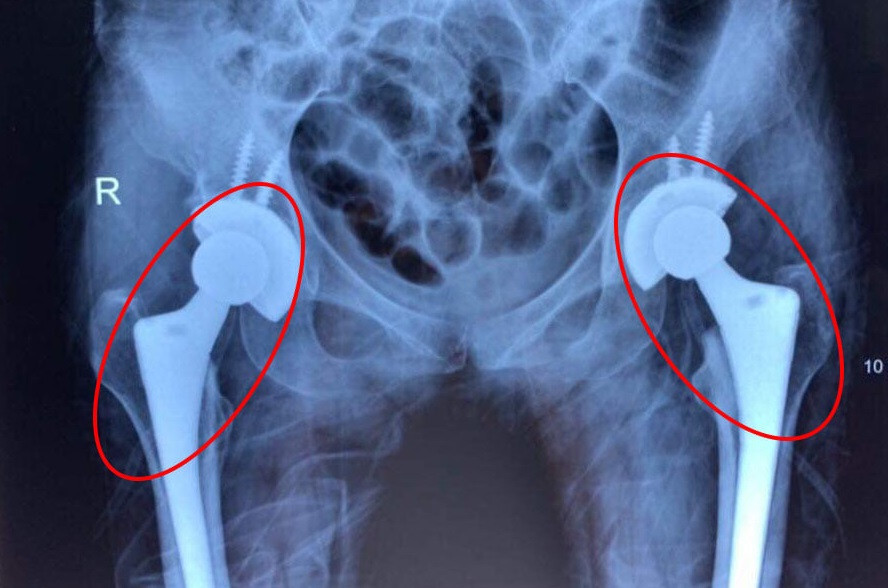

| Nhiều bệnh nhân còn rất trẻ nhưng đã phải thay cả 2 khớp háng do bị mục xương |

Trước đây, bệnh nhân bị mục khớp háng cả hai bên thường phải thay từng khớp một. Hạn chế của kỹ thuật trên là khiến người bệnh chịu nhiều lần đau đớn khi phẫu thuật và phát sinh thêm nhiều khoản chi phí. Hiện nay, với những tiến bộ về chuyên môn và dụng cụ y khoa các bác sĩ có thể thay khớp háng cả 2 bên cho người bệnh trong cùng một cuộc mổ không chỉ giúp bệnh nhân tiết kiệm được chi phí mà còn giúp người bệnh nhanh chóng bình phục, cải thiện chất lượng cuộc sống cho người bệnh.

BS Lãm cho biết, trong số 10 ca bệnh đã thay 2 khớp háng tại Bệnh viện Hoàn Mỹ Sài Gòn, hầu hết là bệnh nhân trẻ tuổi, chỉ khoảng 2 đến 3 tháng sau ca mổ bệnh nhân đã có thể vận động bình thường trở lại. Tuy nhiên, khớp nhân tạo chỉ có thể sử dụng khoảng 25 đến 30 năm. Người trẻ tuổi thường phải mổ lại để thay khớp khác, việc phẫu thuật lần 2 là thách thức với các bác sĩ và người bệnh bởi nguy cơ tai biến, biến chứng ở mức cao.